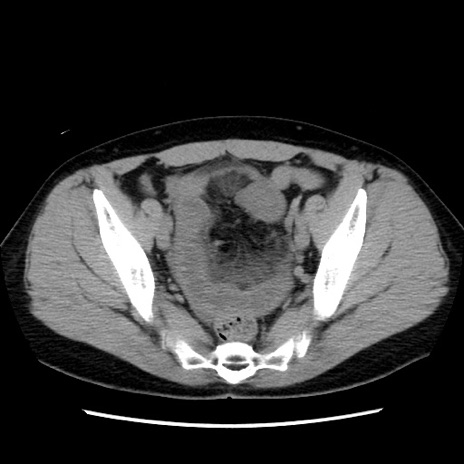

症例10(横断像)

【症例】 50歳代女性

【主訴】 腹痛

【現病歴】前日生レバーを食べた。今朝に排便あり。 昼前に突然発症の腹痛を生じ、当院救急外来を受診した。

【既往歴】 子宮筋腫にてで子宮全摘後

【身体所見】 意識清明、腹部:平坦、軟、下腹部やや左を中心に圧痛・反跳痛あり、筋性防御あり

【データ】WBC 7800、CRP 0.07